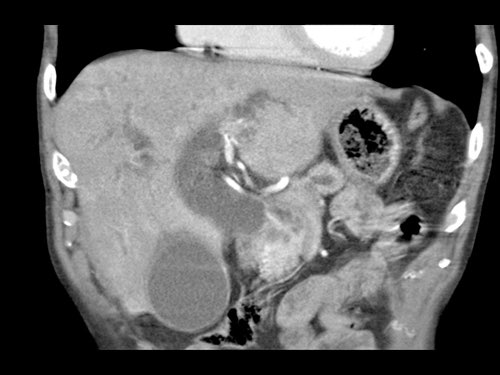

Ở những bệnh nhân dự kiến phẫu thuật tụy, điều quan trọng là cần đặc biệt chú ý tìm kiếm nguyên ủy bất thường của động mạch gan phải hoặc động mạch gan chung.

Các động mạch này xuất phát từ phía phải của động mạch mạc treo tràng trên (SMA) và đi qua vùng lân cận đầu tụy, làm tăng nguy cơ xâm lấn của khối u hoặc tổn thương do phẫu thuật.

Tần suất được ghi nhận của các bất thường đặc hiệu này lần lượt là 11-21% và 0,5-5%.

Sự liên quan mạch máu được đánh giá rõ hơn trên ảnh tái tạo mặt phẳng đứng dọc. Có sự áp sát 90 – 180° của động mạch gan phải thay thế (mũi tên trắng) bởi ung thư biểu mô tuyến đầu tụy (đầu mũi tên trắng).

Động mạch gan trái nguyên bản đi theo hướng ra trước hơn, tĩnh mạch cửa nằm ở giữa.

Cuộc phẫu thuật là cắt bỏ diện R1.

Các hình ảnh axial của cùng bệnh nhân có chú thích.